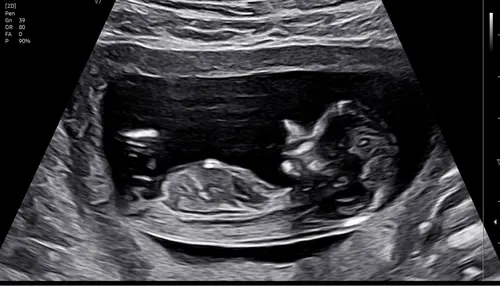

Iemand die hier iets uit kan halen? Ik zie het zelf niet..

Ik kan het niet goed zien helaas!

Iemand idee 13+5 🥰